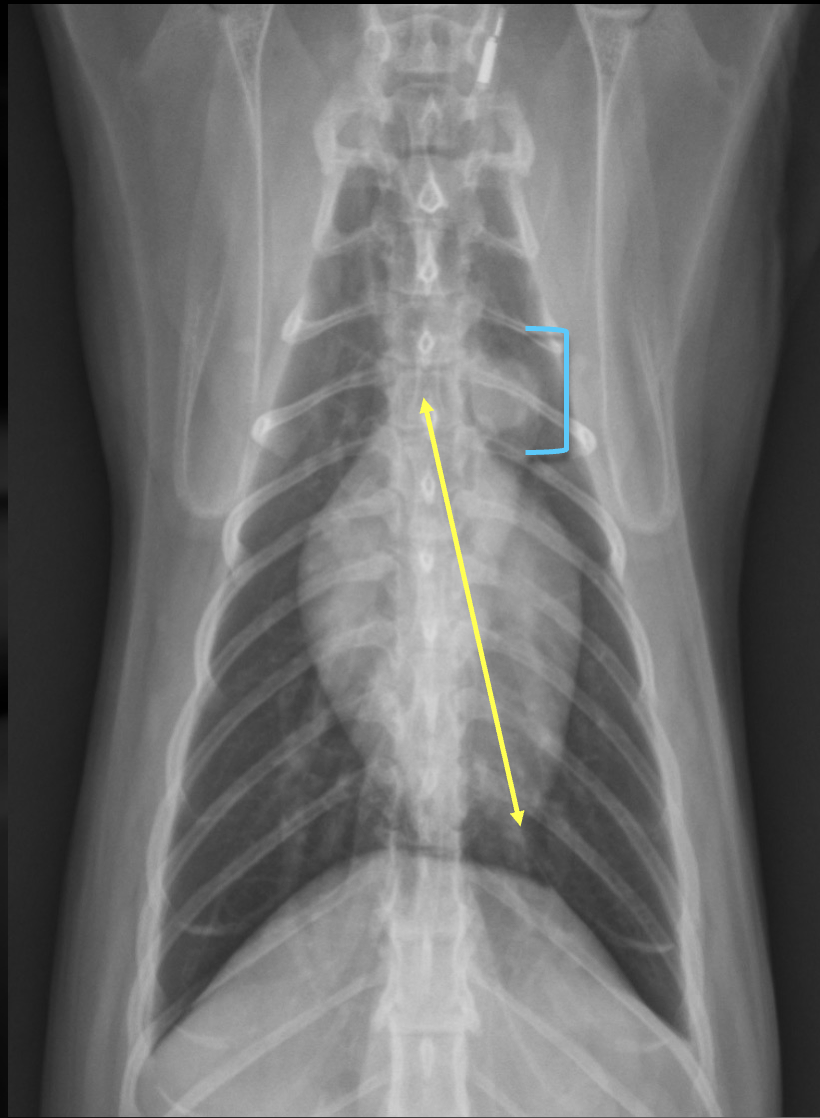

20

What are the normal characteristics of the feline heart in a lateral view?

-heart height is ~ 2/3 of the diameter from dorsal to ventral chest (yellow)

-heart is 2 to 2.5 intercostal spaces wide (pink)

-trachea deviates from spine (blue)